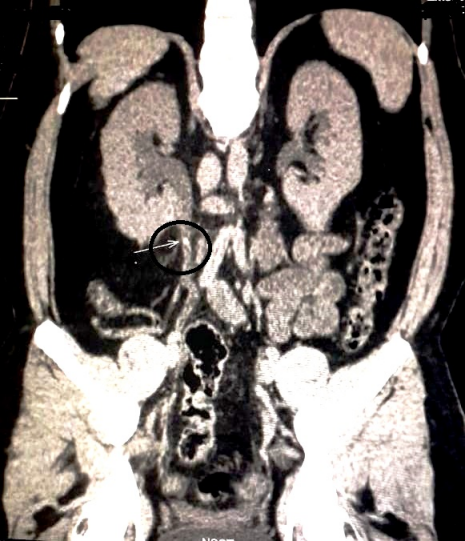

A 31-year-old male of Asian-Indian origin presented to the outpatient department with a one-year history of dull aching right-sided flank pain. There were associated symptoms of abdominal distension and difficulty in voiding urine for the same duration. There was no history of polyuria, graveluria, hematuria or dysuria. On examination, right costovertebral angle tenderness was noted. General and systemic examinations were unremarkable. No lymphadenopathy was noted. On investigation, complete blood count and liver and renal function tests were within normal limits. Urine microscopy showed increased pus cells (20–30/high power field); there were no red blood cells, casts, crystals or malignant cells. Ultrasonography of kidney, ureter and bladder region revealed right-sided hydronephrosis. Computed tomography (CT) scan revealed a hyperdense mass of 2.3x4.6 mm in the right renal pelvis with severe hydronephrosis and cortical thinning (Figure 1 [Fig. 1]). Renal dynamic scan revealed a poorly functioning right-sided kidney. Considering the poor functional status, right-sided nephrectomy was performed and the specimen was sent for histopathological examination. On gross examination, the kidney measured 11x8x5 cm with a cut surface showing dilated pelvicalyceal system filled with slimy watery fluid; the renal pelvis was thickened with a greyish-white cut surface. Multiple stones were noted in the pelvis and kidney parenchyma. Microscopic examination revealed features of chronic pyelonephritis; the adjacent renal pelvis showed pseudostratified columnar epithelial metaplasia with presence of tumor cells arranged in the form of glands and suspended in mucin pools. The tumor infiltrated lamina propria and superficial layers of the muscle coat of the renal pelvis (Figure 2 [Fig. 2], Figure 3 [Fig. 3], Figure 4 [Fig. 4], Figure 5 [Fig. 5]). Adenocarcinoma in situ was noted in the adjacent ureter (Figure 6 [Fig. 6]). Pathological TNM staging was pT2aNxMx.

Figure 1: Computed tomography (CT) of the abdomen showing a mass lesion in the right renal pelvis